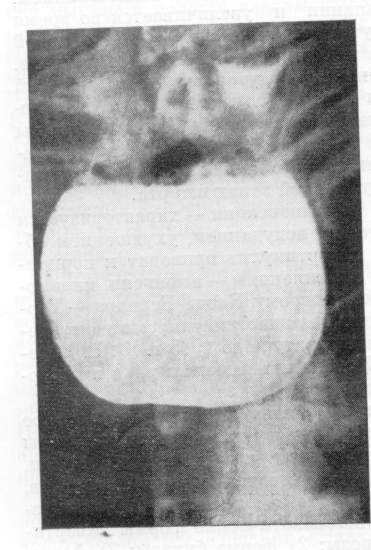

Основной метод выявления эпифренальных дивертикулов - контрастное рентгенологическое исследование (рис. 7) и эзофагоскопия.

Рис. 7. Рентгенограмма. Приобретенный эпифренальный дивертикул и симптоматическая ахалазия кардии. А – передняя; б – боковая проекция.